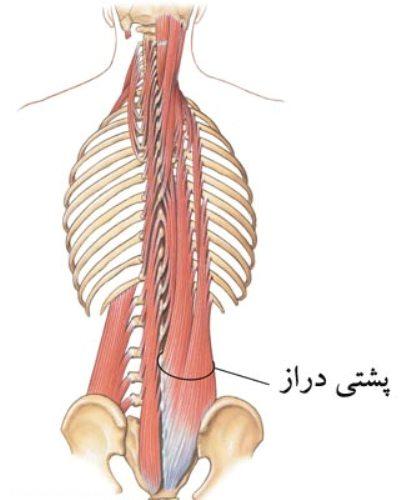

عضله پشتی دراز

عضله ای طویل است که از استخوان پس سری تا خاجی کشیده می شود. این عضله از روی استخوان خاجی، زوائد خلفی مهره های کمری، تاج خاصره شروع شده و با توجه به محل چسبندگی انتهای دیگر تارها به سه گروه عضلانی تقسیم می گردد:

۱- خاصره ای، که روی دنده ها کشیده می شود.

۲- طویل، که روی زوائد عرضی مهره ها کشیده می شود.

۳- شوکی که روی زوائد شوکی مهرها کشیده می شود.